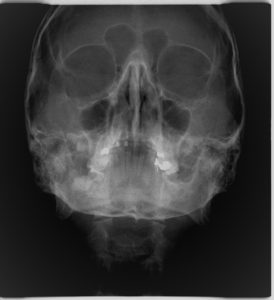

3. ΟΠΙΣΘΟΠΡΟΣΘΙΑ ΚΕΦΑΛΟΜΕΤΡΙΚΗ ΑΚΤΙΝΟΓΡΑΦΙΑ

Η οπισθοπρόσθια ακτινογραφία είναι μια κατά μέτωπο ακτινογραφία του κρανίου.

Δίνει τη δυνατότητα αξιολόγησης πιθανής ασυμμετρίας μεταξύ του δεξιού και αριστερού ημιμορίου της άνω και κάτω γνάθου. Επίσης με αυτήν απεικονίζονται και αξιολογούνται οστικά κατάγματα της κάτω γνάθου που μπορεί να εντοπίζονται στο σώμα, τον κλάδο ή τη γωνία αυτής.

Η λήψη της είναι γρήγορη (διαρκεί λίγα δευτερόλεπτα) και ανώδυνη.